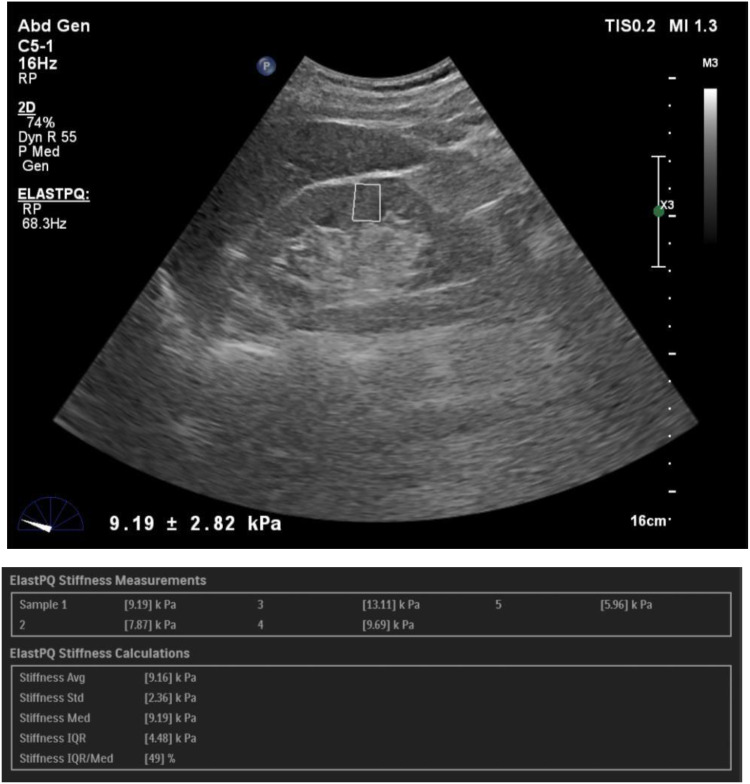

Materials and methods: The study protocol was approved by the Institutional ethics Committee at Kasturba medical college, Manipal and written informed consent was obtained from all participants. The study included 93 control subjects and 108 patients with CKD. SWE imaging was performed to assess renal cortical stiffness, as measured by the Young's modulus (YM). Correlations between SWE and conventional ultrasound parameters with age, serum creatinine, eGFR and serum urea were analysed using Pearson's correlation coefficient (p ≤ 0.05) and receiver operating characteristic (ROC) curves were derived.

Results: The diagnostic performance of SWE correlated with serum creatinine levels and eGFR. We found a statistically significant difference in kidney stiffness values between healthy individuals and CKD patients. The Spearman correlation coefficient revealed moderate negative linear correlation between the YM measurements and eGFR. We obtained a YM measurement cut-off value of 4.43 kPa, a value less than or equal to this suggested a no diseased kidney. This yielded sensitivity and specificity of 92.6% and 80.6%, respectively, with an AUROC of 0.92.